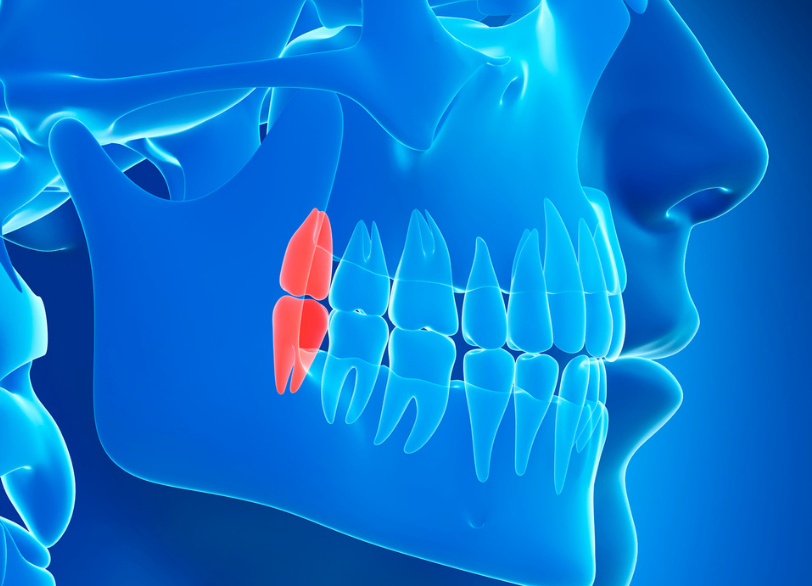

親知らずとは前歯から数えて8番目、一番奥に生えてくる永久歯のことです。 正式には「第三大臼歯(だいさんだいきゅうし)」、あるいは「智歯(ちし)」とも呼ばれます。 10代後半から20代前半頃、親がその存在を知らないうちに生えてくることから「親知らず」という名前で呼ばれるようになったと言われています。

現代人は食生活の変化などから顎が小さくなる傾向にあり、親知らずがきちんと生えるための十分なスペースがない方がほとんどです。 そのため、横や斜めを向いて傾いて生えてきたり、骨の中に埋まったまま出てこられなかったりと正常に機能していないケースが非常に多く見られます。

横向きに生えた親知らずが、手前の歯を前へ前へと押し続けることで時間をかけて前歯の歯並びが少しずつガタガタになってくることがあります。 特に、一度矯正治療できれいにした歯並びが親知らずの影響で後戻りしてしまうケースも少なくありません。